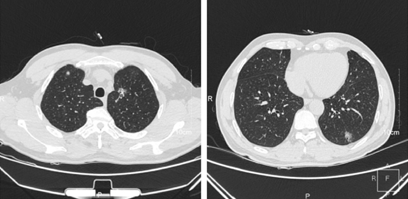

CT是显示GGN的首选方法。对于GGN良恶性的鉴别,需要根据结节的大小、形态、边缘及瘤-肺界面,结节内部密度特征,内部结构特征,瘤周结构以及病灶随访观察等表现综合分析做出正确的诊断和鉴别。

随着结节体积增大,GGN的恶性或浸润性概率增加;大多数恶性GGN的整体形态为圆形或类圆形,结节边缘多呈分叶状,或有毛刺征(又称棘状突起),结节边缘清楚但不整齐,瘤-肺界面清晰、毛糙甚至有毛刺。

GGN密度较高、不均匀提示恶性可能性大;持续存在的GGN大多数为恶性,或有恶性发展倾向。GGN的平均CT值对鉴别诊断具有重要价值,密度高恶性概率大,密度低恶性概率小,同时需要结合结节大小和形态变化来综合判断。